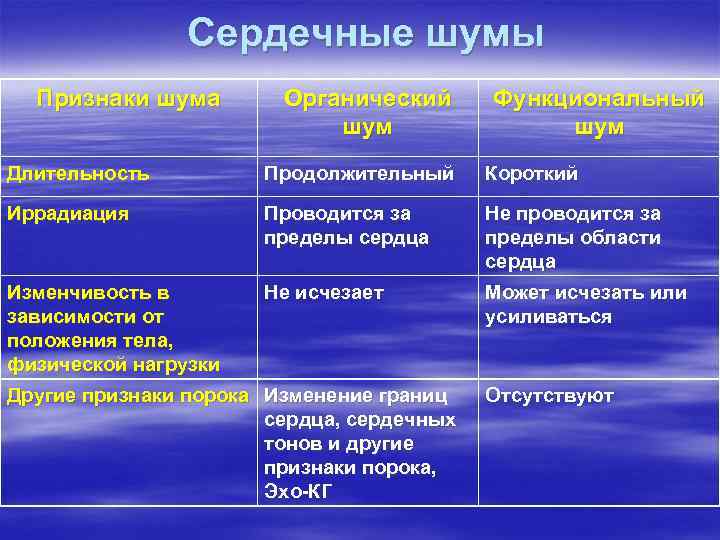

Сердечные шумы Признаки шума Органический шум Функциональный шум Длительность Продолжительный Короткий Иррадиация Проводится за пределы сердца Не проводится за пределы области сердца Изменчивость в зависимости от положения тела, физической нагрузки Не исчезает Может исчезать или усиливаться Другие признаки порока Изменение границ сердца, сердечных тонов и другие признаки порока, Эхо-КГ Отсутствуют

Сердечные шумы Признаки шума Органический шум Функциональный шум Длительность Продолжительный Короткий Иррадиация Проводится за пределы сердца Не проводится за пределы области сердца Изменчивость в зависимости от положения тела, физической нагрузки Не исчезает Может исчезать или усиливаться Другие признаки порока Изменение границ сердца, сердечных тонов и другие признаки порока, Эхо-КГ Отсутствуют